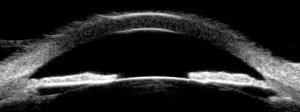

Optical coherence tomography (OCT) is a widely used imaging device in ophthalmology and has been evolving since its first publication in 1991 by Huang et al.[13] This non-invasive imaging technique is capable of providing high-quality cross-sectional images based on the reflectance of tissue using a near-infrared light, in contrast to UBM that uses sound. Its application in the AS was first reported in 1994 and recently is a useful tool with the ability of anatomic and structural measurement with an axial resolution of 5-10µm, lateral resolution of 15-25µm and tissue penetration of 3-6mm.[14] Other advantages are its non-contact principal, fast acquisition and does not require experienced operators.

AS-OCT can also provide quantitative measurements and is used in keratoconus diagnosis, corneal refractive surgery, corneal transplant surgery, and other ocular surface diseases including tumors.

AS-OCT can also generate up to 10mm corneal diameter CT and ET maps by performing high resolution scans on 8 meridians of the cornea, with automated software that reconstructs the cornea 3-dimensionally.[15] Both CT and ET have shown a strong correlation to the gold standard ultrassound respective measurements with a high reproducibility and repeatability.[16] [17]